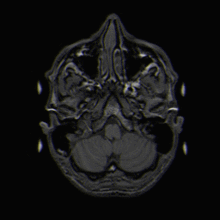

Einzelbild einer Magnetresonanz- tomographie eines menschlichen Gehirns -

Schnitt durch den Kopf eines Menschen, die Nase befindet sich links; animierte Version mehrerer sagittaler Schnittebenen -